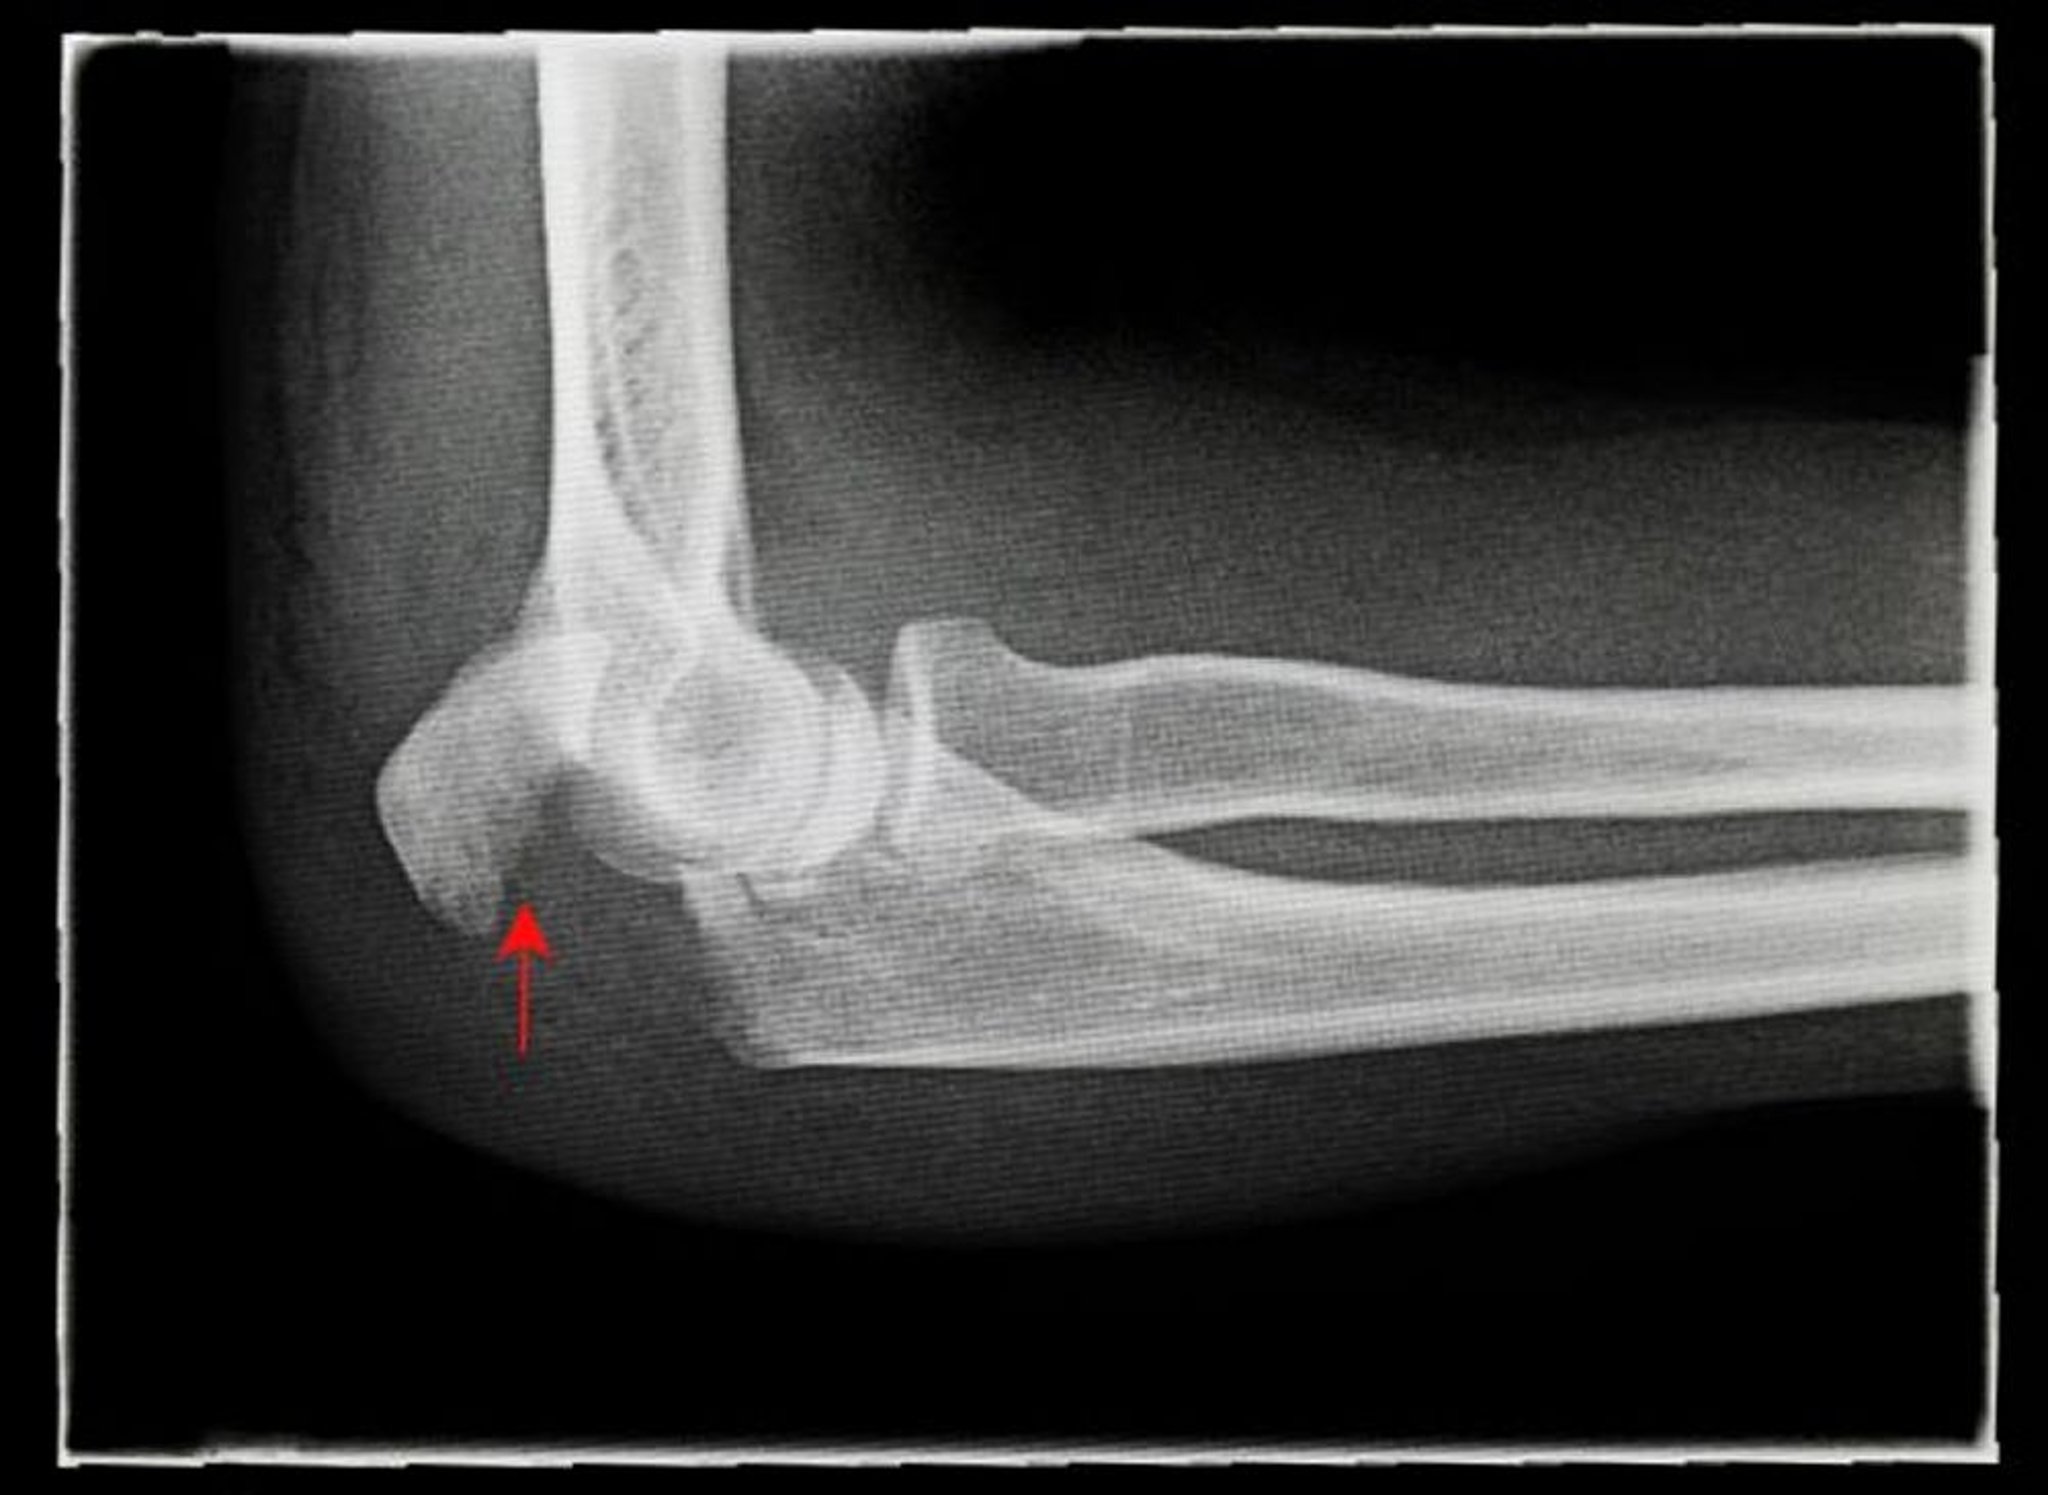

Fractura desplazada del olécranon

Esta radiografía muestra una vista lateral de una fractura desplazada del olécranon (flecha).